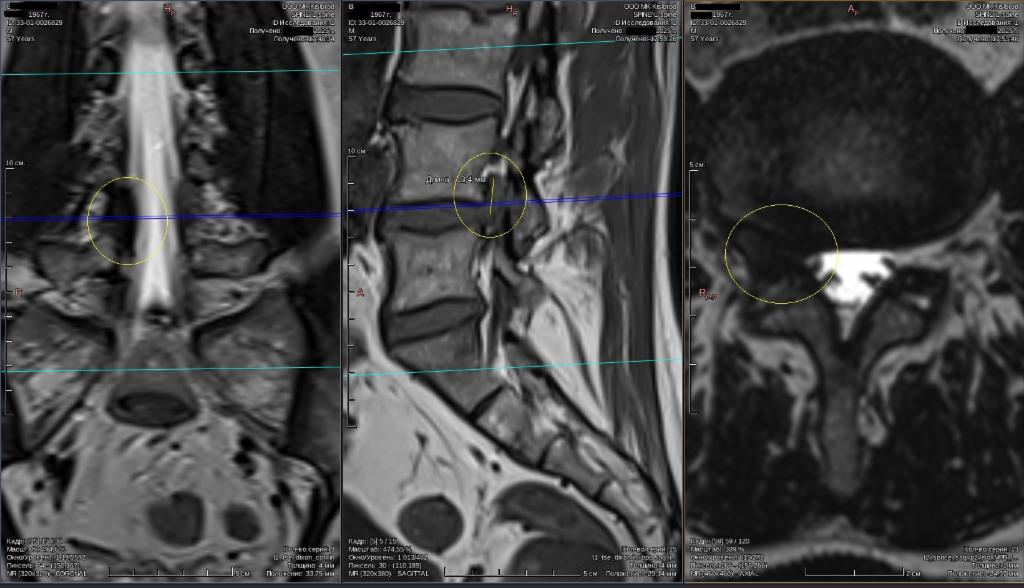

Грыжа Диска L5 S1 Фото

Грыжа Диска L5 S1 Фото 108 фотографий